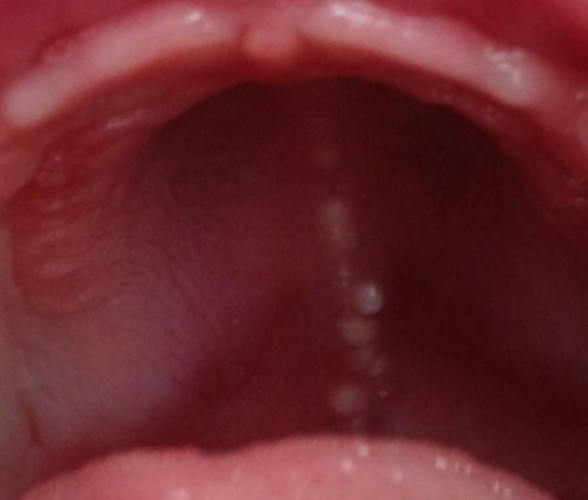

咽喉白色念珠菌感染